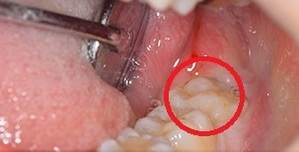

まっすぐ生えている親知らず

まっすぐ生えている親知らずは一見何の問題も無いように見えることが多いですが歯ブラシが届きにくく汚れがたまりやすいため実は虫歯や歯周病になっていることが多いです。

このケースでは赤い枠の中の親知らずが大きな虫歯と根の病気・さらには歯周病にもかかっており痛みがありました。

口腔内写真

真っ直ぐ生えた親知らず